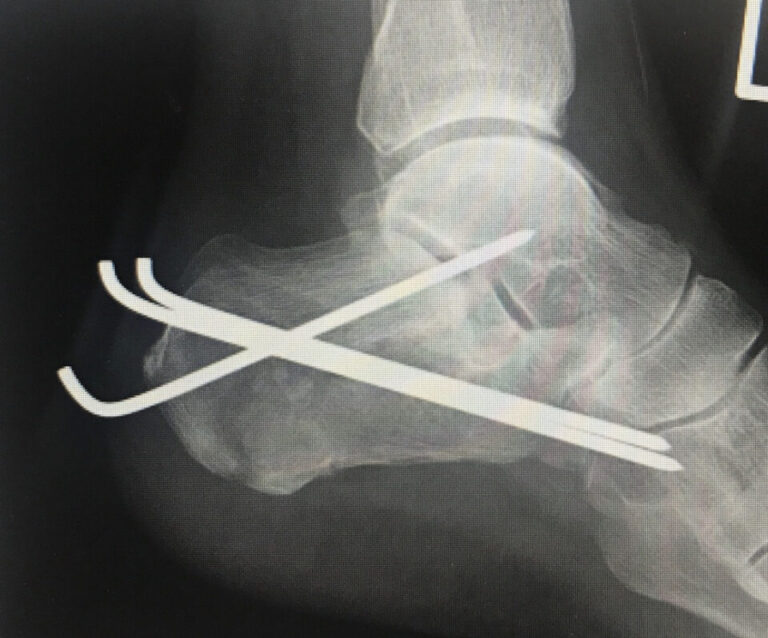

舌状変形の踵骨骨折に対する手術法でもっともポピュラーなものになります。

当院ではスタイマンピンは整復のみに使用しています。なぜなら抜釘したときに血がでてとまらなくなるからです・・・・

整復したのちは2.4mmのKワイヤーを数本、立方骨と距骨に向けて挿入して固定しています。これなら抜釘したときも大きな穴ができません。